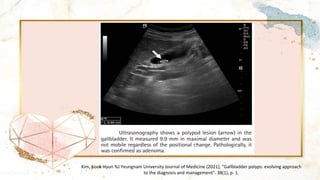

Ultrasonography

• Hyperechoic lesions protruding into the GB lumen

• Absence of post-acoustic shadow

• A fixed lesion helps to distinguish between polyps and

gallstones

• “Pseudo” polyp include a “comet tail” which arises

posterior to the lesion but not in all